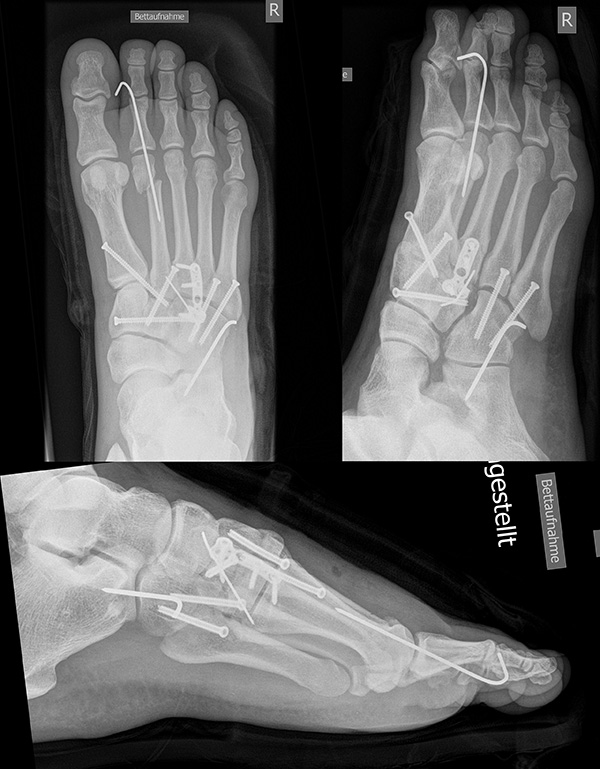

In der Regel werden die physiologisch rigiden TMT-1 bis 3 mittels Schrauben transfixiert. Hierfür werden meist kanülierte Kleinfragment-Kortikalisschrauben (3,5 oder 4 mm) verwendet. Diese können in Stellschraubentechnik von der Metatarsale-1-Basis in das Os cuneiforme mediale (Abb. 17) sowie vom Os cuneifome mediale in die Metatarsale-2-Basis und bei zusätzlicher intercuneiformer Instabilität vom Os cuneifome mediale in das Os cuneifome intermedium eingebracht werden.

Zum Lesen der Bildbeschreibung und zur Vollansicht bitte das Bild anklicken.

Ggf. wird zusätzlich ein K-Draht oder eine Schraube von der Metatarsale-2-Basis in das Os cuneiforme intermedium gebohrt (Abb. 18). Zur Transfixation der TMT-4 und 5-Gelenke werden, entsprechend ihres höheren physiologischen Bewegungsumfangs meist K-Drähte empfohlen. Die Indikation zur Transfixation wird von den meisten Autoren nur bei einer Instabilität gesehen, einige empfehlen eine Transfixation sämtlicher TMT-Gelenke unabhängig vom Ausmaß der Instabilität 10. Kleine, nicht refixierbare Fragmente sollten entfernt werden. Ist ein primärer Hautverschluss nicht möglich, erfolgt die temporäre Weichteildeckung mit Kunsthaut wie Epigard 112951710.